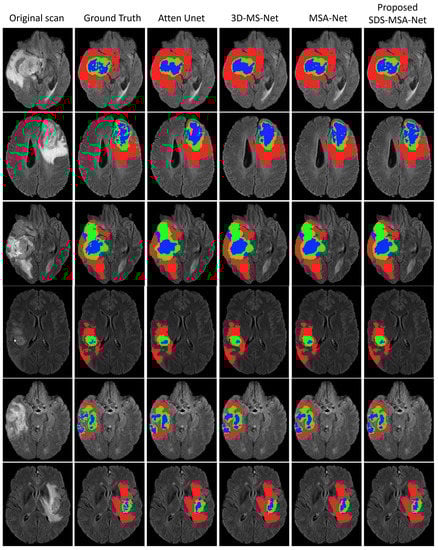

4.3. Qualitative Analysis

4.4. Overall Performance Analysis